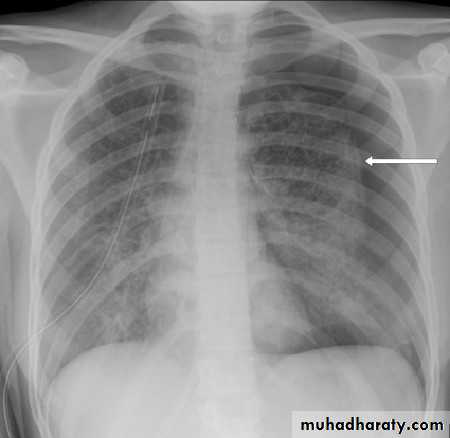

PNX in

Diseased lungDiseases of the Pleura Dr.Mustafa Nema. Baghdad College of Medicine 2013